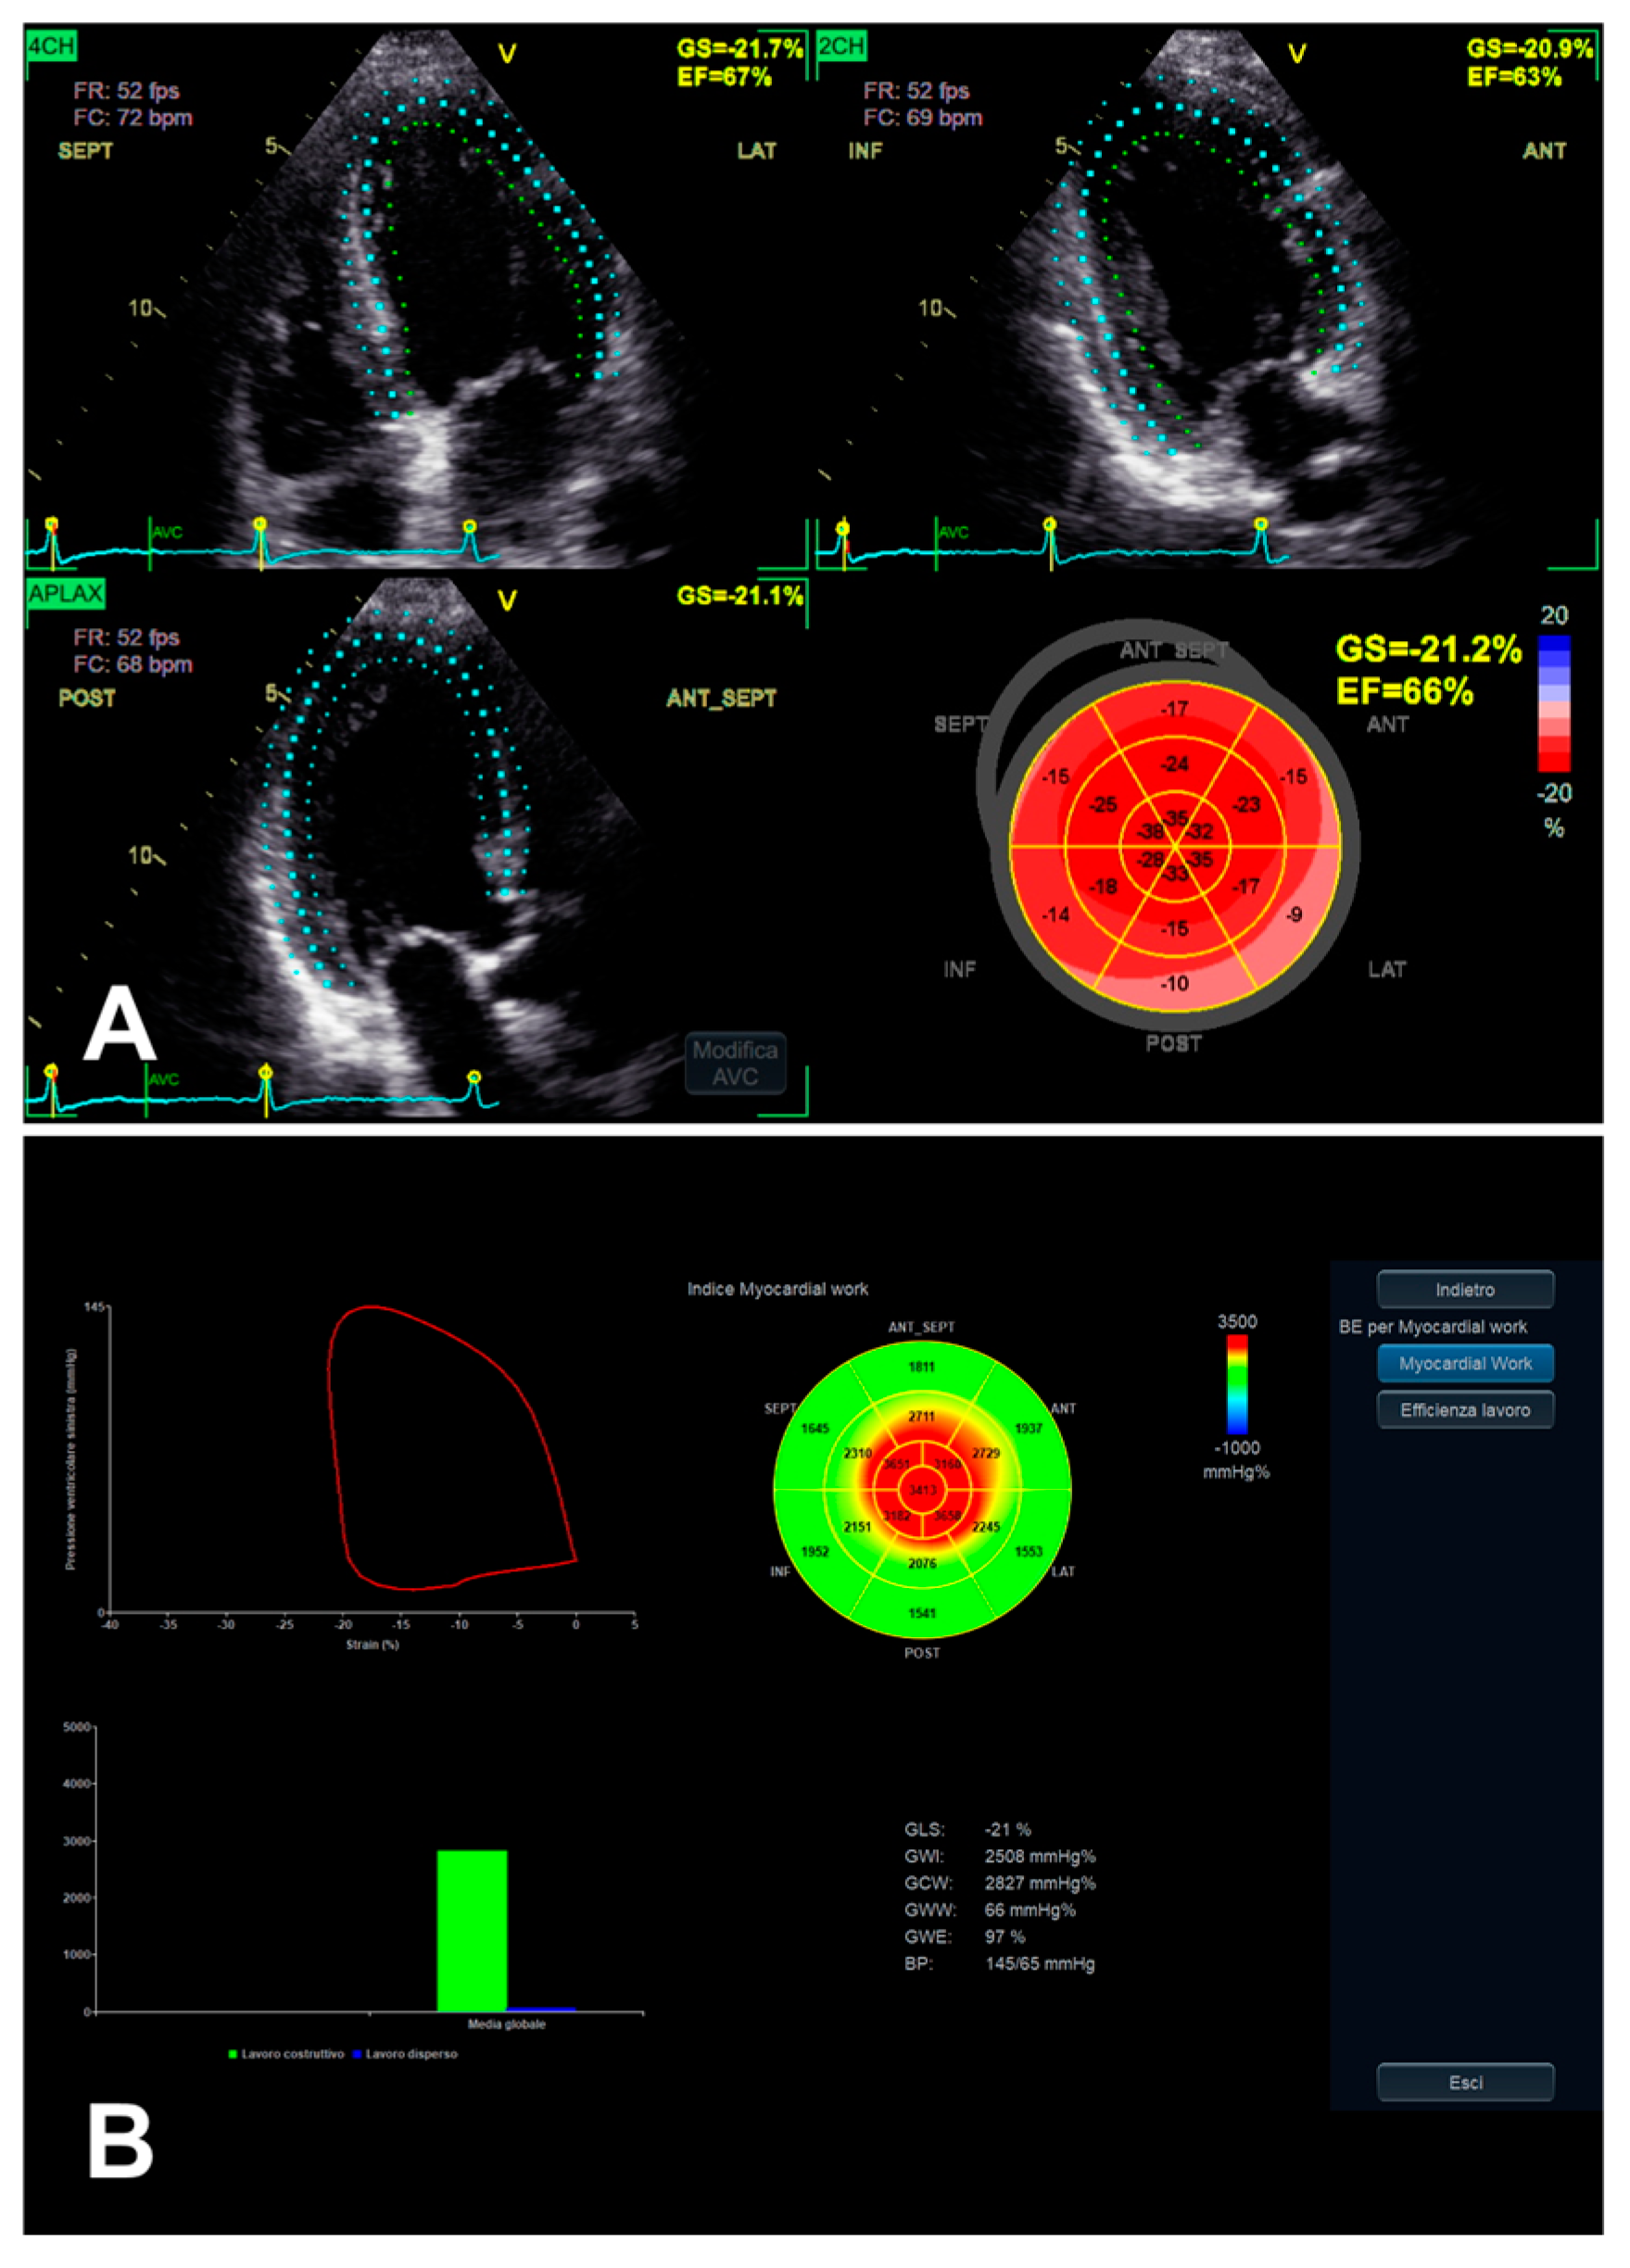

3.3. Left Ventricular Myocardial Work

| LV MW | GCW | Positive work evaluated from AVO to AVC and negative work from AVC to MVO | - Relatively low intra and inter-observer variability (if good US window). | - GLS-related limits (including image quality); - AP measurement-related limits; - Single available software. |

| GWI | Total work evaluated from MVC to MVO | |||

| GWE | GCW/(GCW + GWW) | |||

| GWW | Positive work evaluated from AVO to AVC and negative work from AVC to MVO |